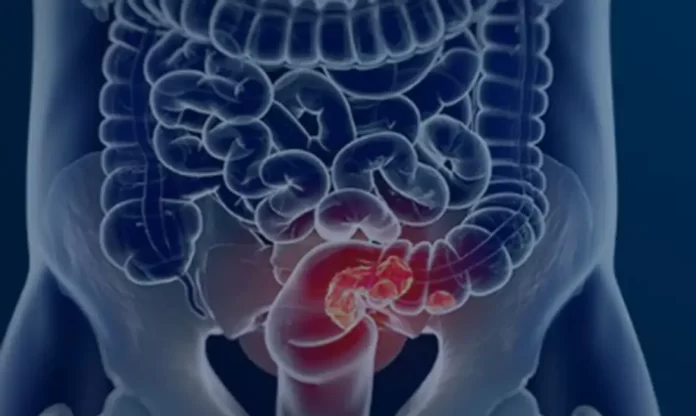

Segundo o coordenador, muitas vezes a doença se desenvolve de forma lenta, a partir de pequenos pontos que ao longo de anos podem se transformar em câncer. Além de sangue nas fezes, os sinais de alerta incluem mudanças do hábito intestinal, como as fezes em fita ou diarreicas, dores abdominais persistentes e perda de peso sem causa aparente.

Os cânceres de cólon e reto, que atingem o intestino, são os terceiros mais frequentes do Brasil, com cerca de 45 mil novos registros por ano, de acordo com a estimativa do Instituto Nacional do Câncer para o triênio de 2023 a 2025.